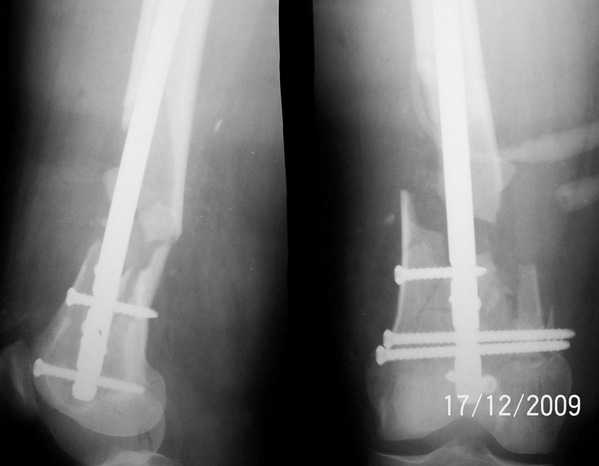

Уважаемые коллеги, прооперирована пациентка антеградным штифтом Остеомед, костная пластика не проводилась. Выбранный штифт по каналу бедренной кости на фоне отсутствия переднего кортикала в канале не центрируется. Технически неприятно, отсутствие передней и внутреннебоковой стенки до зоны мыщелков сильно затрудняло репозицию. Получилась вот такая картина. После стабилизации - очевидное повреждение ПКС и боковая нестабильность. В общем и далее будет чем заняться. Нам и в дальнейшем будет очень интересно мнение коллег.